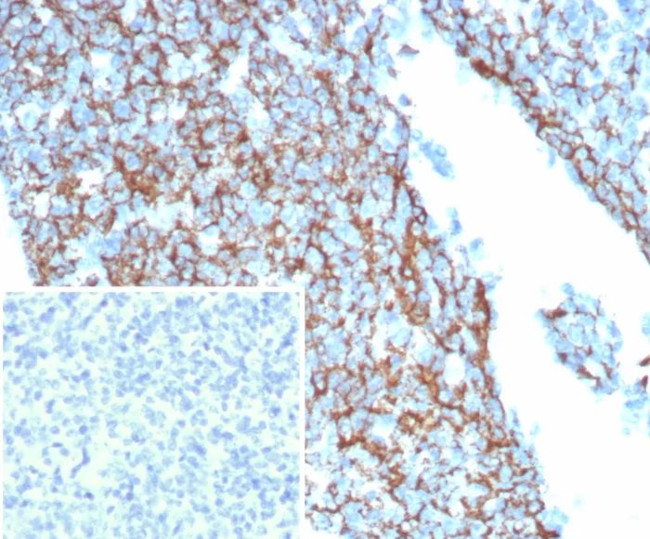

CD35/CR1 (Follicular Dendritic Cell Marker) Antibody in Immunohistochemistry (Paraffin) (IHC (P))

CD35/CR1 (Follicular Dendritic Cell Marker) Antibody (1378-RBM20-P1) in IHC (P)

Formalin-fixed, paraffin-embedded human tonsil stained with CD35 Recombinant Rabbit Monoclonal Antibody (CR1/8244R). Inset: PBS instead of primary antibody; secondary only negative control. {{ $ctrl.currentElement.advancedVerification.fullName }} 验证信息 View more